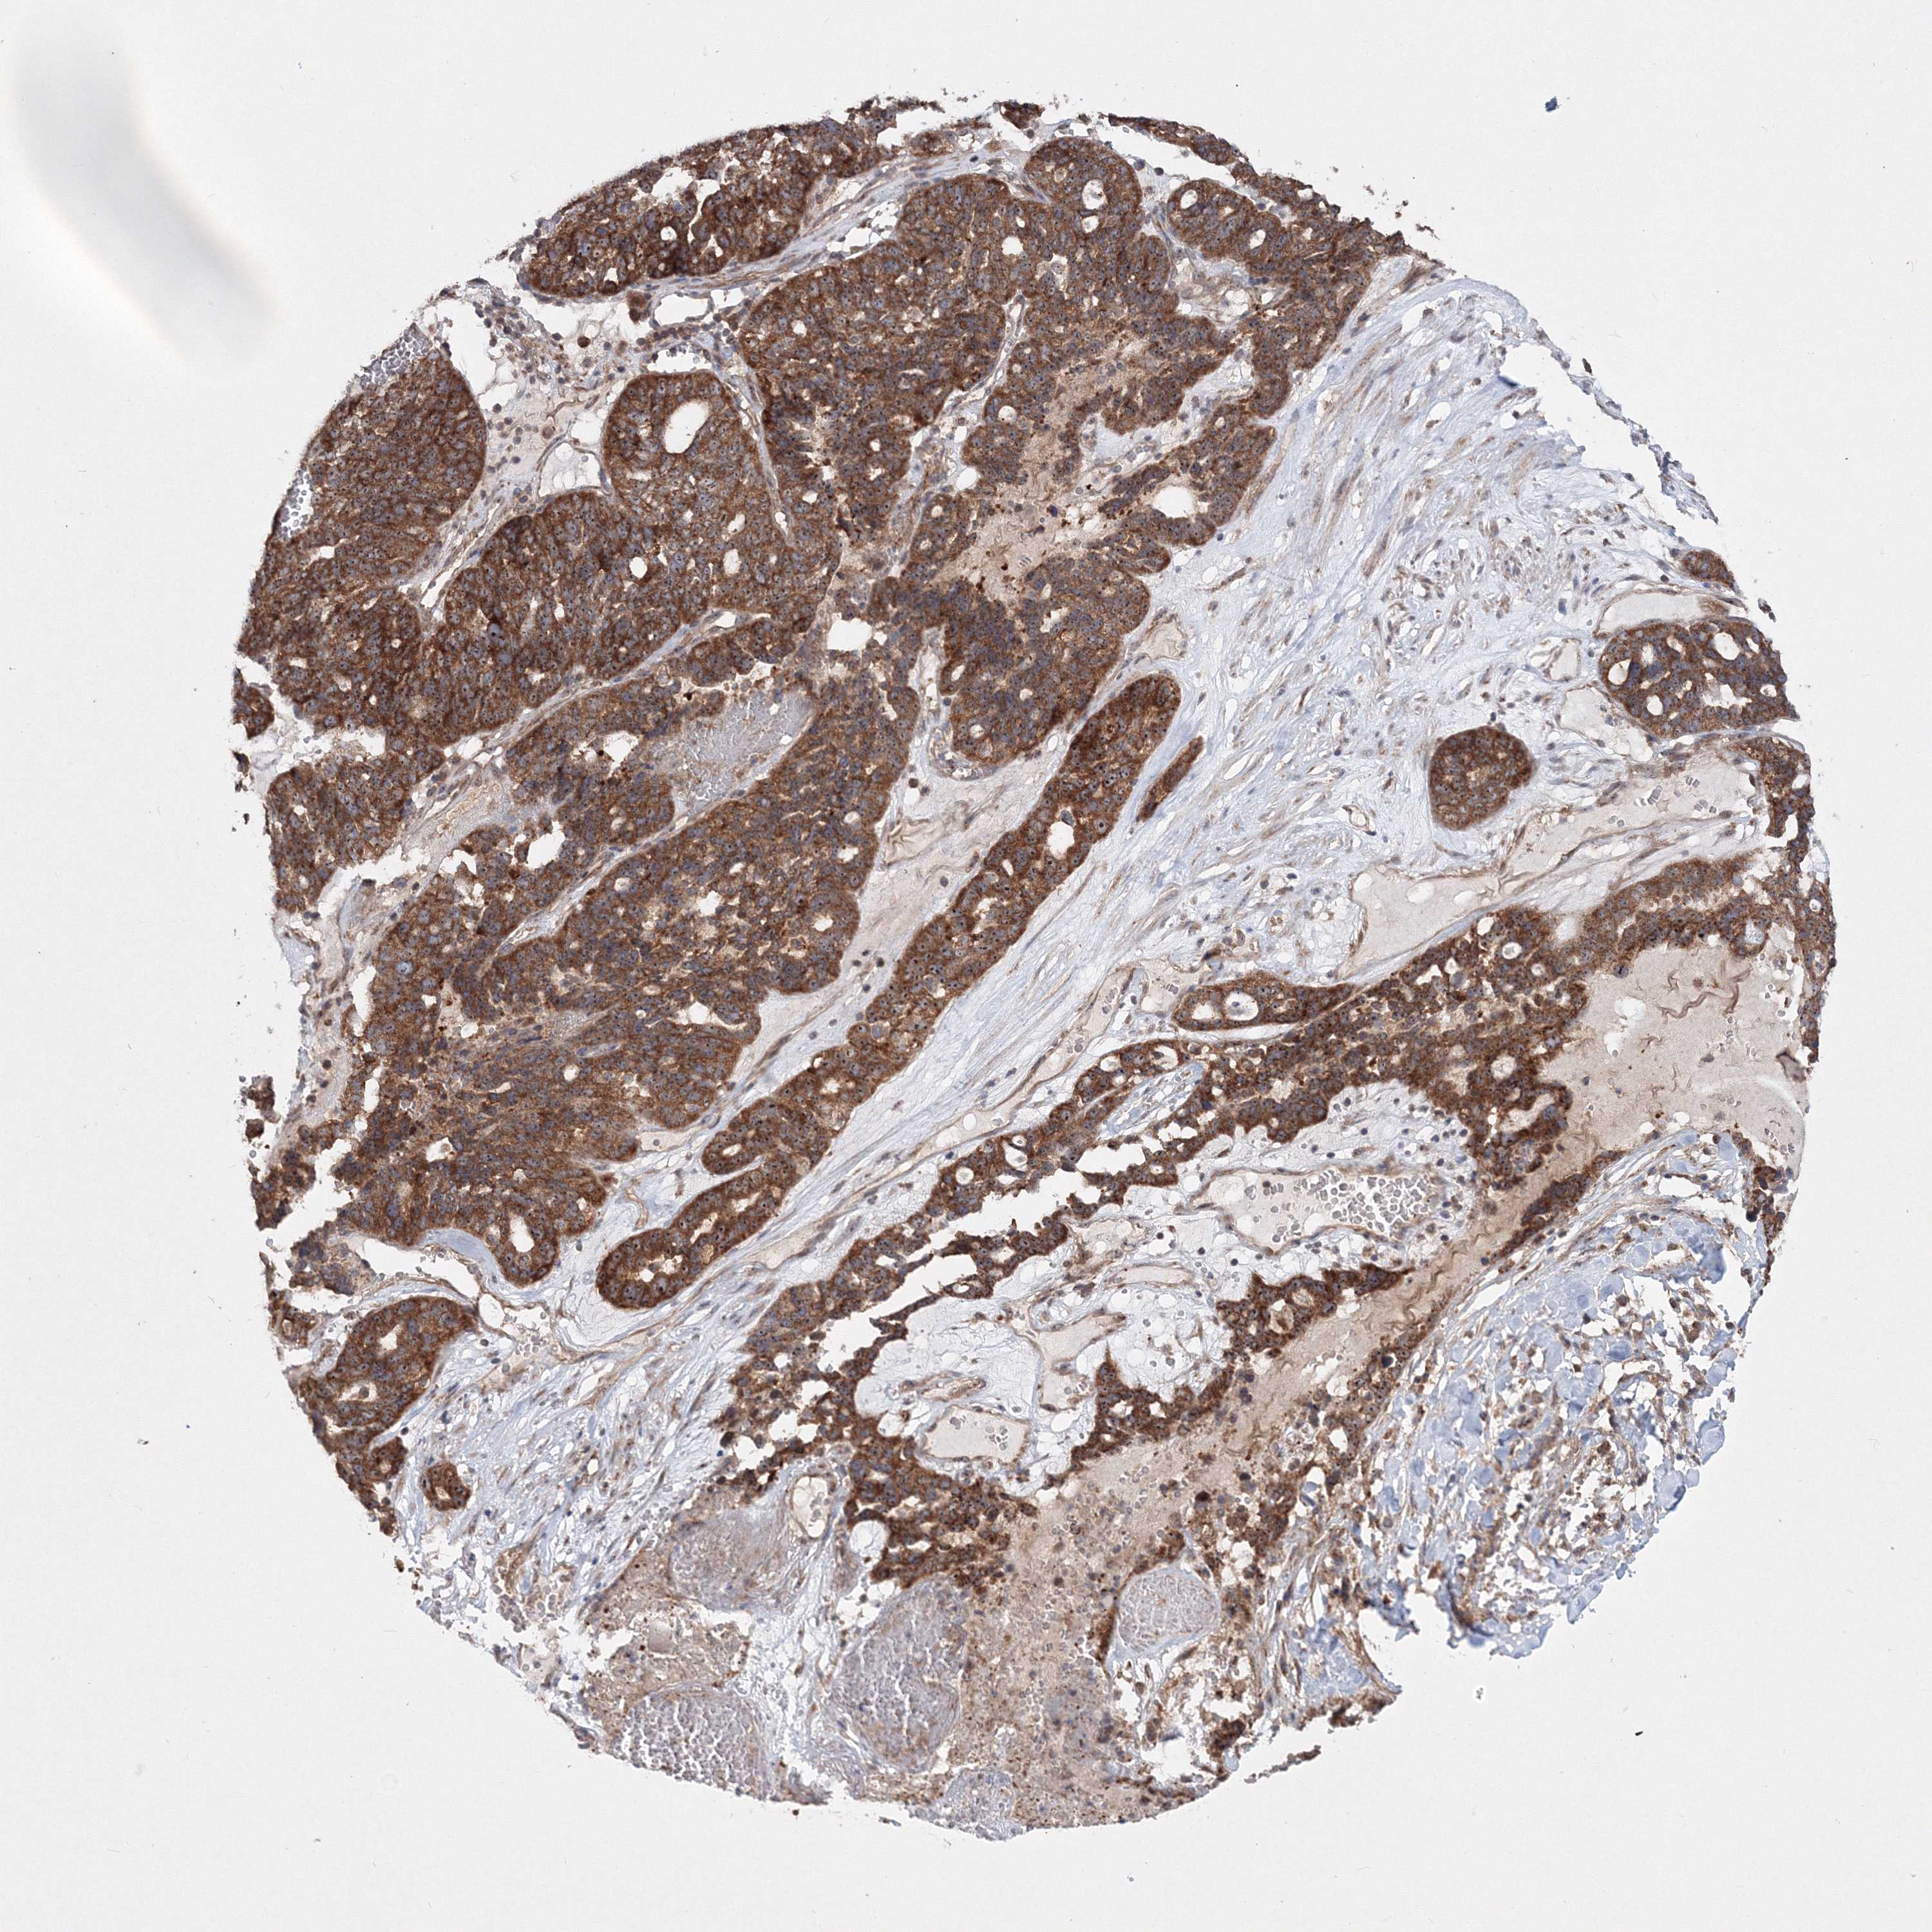

OVARIAN CANCER - Protein expressioni

A mouse-over function shows sample information and annotation data. Click on an image to view it in a full screen mode. Samples can be filtered based on level of antibody staining by selecting one or several of the following categories: high, medium, low and not detected. The assay and annotation is described here.

Note that samples used for immunohistochemistry by the Human Protein Atlas do not correspond to samples in the TCGA dataset.

Antibody stainingi

Antibody staining in the annotated cell types in the current human tissue is reported as not detected, low, medium, or high, based on conventional immunohistochemistry profiling in selected tissues. This score is based on the combination of the staining intensity and fraction of stained cells.

Each image is clickable and will lead to virtual microscopy that enables deeper exploration of all samples and also displays staining intensity scores, fraction scores and subcellular localization as well as patient and tissue information for each sample.

Antibody HPA032141

Antibody HPA032142

Antibody CAB032689

Staining

High

Medium

Low

Not detected

Intensity

Strong

Moderate

Weak

Negative

Quantity

>75%

75%-25%

<25%

None

Location

Nuclear

Cytoplasmic/membranous

Cytoplasmic/membranous,nuclear

Cystadenocarcinoma, serous, NOS

Carcinoma, endometroid

Cystadenocarcinoma, mucinous, NOS

Carcinoma, NOS